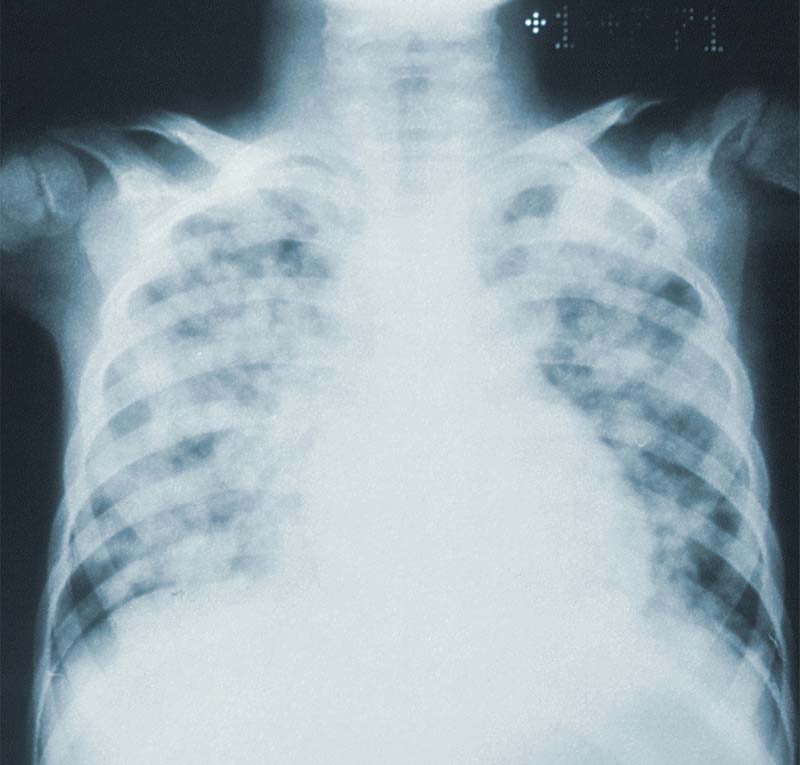

Acute respiratory distress syndrome (ARDS) is a life-threatening form of non-cardiogenic respiratory failure that affects both children and adults, typically arising in the setting of severe illness, trauma, or sepsis. The syndrome results from diffuse alveolar-capillary membrane damage, triggered by systemic inflammation, aspiration, infection, or trauma. This cascade leads to increased alveolar permeability, pulmonary edema, loss of surfactant, and impaired lung compliance, causing severe ventilation–perfusion (V/Q) mismatch and hypoxemia. The consequences include multiorgan dysfunction, prolonged mechanical ventilation, and high mortality, with survivors at risk for long-term pulmonary and neurocognitive impairments.